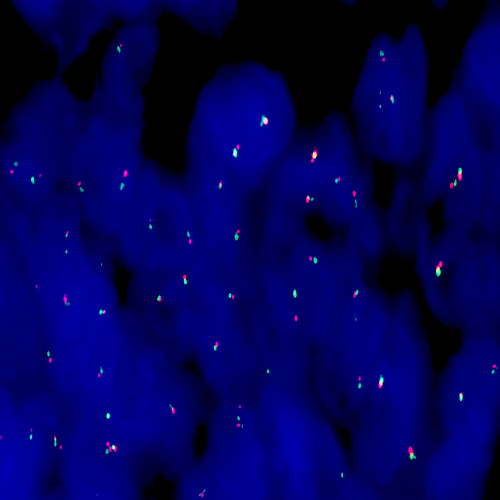

Hybridization of MET Amplification probe to a tissue section showing MET amplification.

The MET proto-oncogene is a receptor-like tyrosine kinase that drives a physiological cellular program important for development, cell movement, cell repair and cellular growth. Aberrant execution of this program has been associated to neoplastic transformation, invasion and metastasis. Activation of MET has been reported in a significant percentage of human cancers including non-small cell lung cancer (NSCLC) and is amplified during the transition between primary tumors and metastasis. The MET (7q31) FISH probe is optimized to detect copy numbers of the MET gene region at region 7q31. The Chromosome 7 Satellite enumeration probe (SE 7) at D7Z1 is included to facilitate chromosome identification.